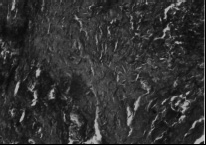

Эпителиальный покров. При гистологическом исследовании препаратов всех групп были выявлены изменения со стороны эпителиального покрова. Они более выражены в лакунах, меньше на зевной поверхности и зависели в значительной мере от длины и ветвистости крипт. Принято, что признаком хронического тонзиллита является значительная ретикуляция эпителия, т.е. разрастание ретикулярной сети в эпителии и обильную инфильтрацию ее лимфоцитами и плазматическими клетками. В наших наблюдениях при токсическом зобе инфильтрация лимфоцитами достигала такой степени, что граница между эпителием и подлежащей тканью перестает определяться (рис.1,2). В некоторых наблюдениях в эпителиальном покрове обнаруживались единичные полиморфноядерные лейкоциты в эпителии крипт, а также папиллярные выросты стенок крипт (рис.3), закрывающие их просвет и тем самым создающие условия для задержки содержимого крипт. Как известно, в развитии хронического тонзиллита .особое значение придается задержке отделяемого крипт. В результате наличия ветвистых извилистых крипт, папиллярных выростов, пробки приводят к сужению и даже полной облитерации устьев крипт (рис.4,5). Задержка со-держимого крипт в отдельных случаях обусловливает расширение их просвета (рис.6), а при полной облитерации некоторые авторы наблюдали образование ретенционных кист (рис.7).

Рис. 3. Папиллярные выросты стенок крипт. Окраска гематоксилин-эозин, ув. х 400 |

Рис. 4. Пробки в полости крипт. Окраска гематоксилин-эозин, ув.х 400 |